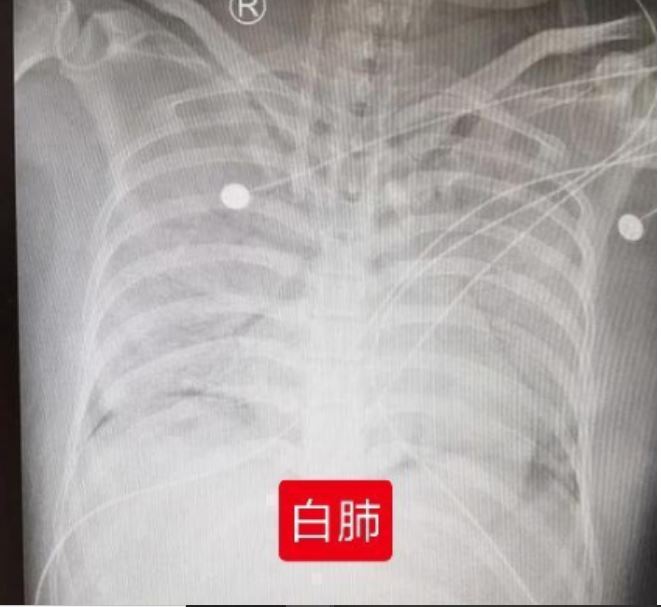

拿防晒喷雾喷脸后狂咳呕吐 7岁女孩照X光 已近“白肺”

(杭州22日综合电)中国浙江杭州一名7岁女童涵涵近日跟著家人到户外游玩时,拿了妈妈的防晒喷雾,往脸上喷了几下后,突然开始狂咳嗽,还将早餐都吐了出来。涵涵的父母急忙将孩子送医救治。浙江医院儿科医师陈国庆检查发现,涵涵的肺部X光结果显示,两肺大片斑块影,已接近“白肺”。

ETtoday新闻云引述《都市快报》报道,陈国庆医师迅速为涵涵安排了,简单的血检和胸部X光检查,胸部X光结果已接近“白肺”,血常规则提示白血球升高、C反应蛋白正常。陈医师表示,以涵涵的病史结合临床表现,基本考量是防晒喷雾吸入后,导致急性过敏性肺炎。